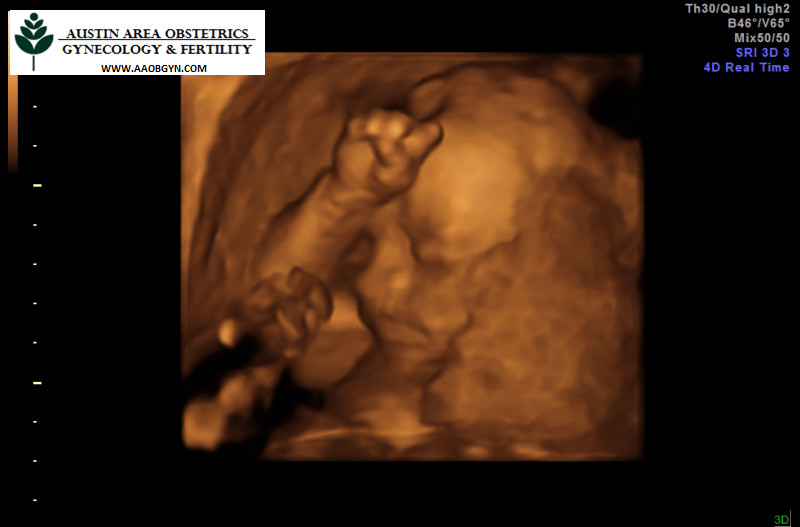

We made it through the MaterniT21 test and the Level II ultrasound and fetal Echo. You are a girl with every appearance of perfect health so far.